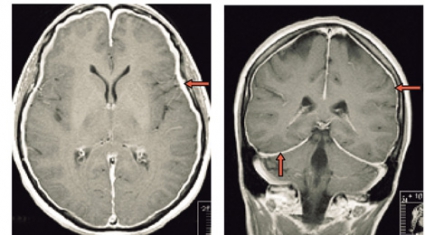

Spontan intrakraniell hypotension är sannolikt ett underdiagnostiserat tillstånd som man bör tänka på hos patienter med nytillkommen daglig huvudvärk, särskilt om den förvärras i stående (Fakta 1). För att ställa diagnos gäller att likvortrycket ska vara lågt, helst <6 cm H2O i liggande, och MRT med kontrast (helst före lumbalpunktion) ska visa generell dural uppladdning (s k pakymeningit) och karakteristiska förändringar av hjärnstammen (Fakta 2) [1, 2]. Initial behandling är symtomlindring med sängläge och gradvis mobilisering. Den kompletteras ofta med rikligt vätskeintag och koffein, antingen i tablettform eller som dropp. Om detta inte ger effekt är epidural injektion av autologt blod (»blood patch«) nästa steg, som ger snabb effekt hos de flesta patienter men som kan behöva upprepas [3]. Vid terapiresistens övervägs utvidgad neuroradiologisk utredning för att lokalisera likvorläckagestället. Då finns möjlighet att upprepa blodinjektionen över själva läckagestället. Om det inte hjälper kan kirurgiskt ingrepp diskuteras [2]. Etiologi och patogenes År 1938 beskrev den tyske läkaren Georg Schaltenbrand det tillstånd som kom att kallas spontan intrakraniell hypotension [4, 5]. Då trodde man att orsaken var minskad produktion av likvor från plexus choroideus eller ökad absorption, men bevis saknades. I dag vet man att tillståndet beror på likvorläckage, sannolikt på grund av en defekt i dura mater. Vid utredning har man kunnat påvisa spinala epidurala cystor (divertiklar) som bedömts ha rupturerat spontant eller vid en plötslig tryckstegring i likvorrummet. Det är också känt att osteofyter och diskbråck kan orsaka läckage genom att erodera duran [6, 7]. I dessa fall kan operation bli nödvändig [8]. Vid kirurgi kan man se många olika durala avvikelser, såsom rifter och meningeala cystor [9-11]. Spontan intrakraniell hypotension uppkommer förmodligen i vissa fall av en kombination av lindrigt trauma och underliggande spinal patologi [2, 12]. Enligt litteraturen har upp till en tredjedel av patienterna en oupptäckt bindvävssjukdom. Många har morfologiska tecken på bindvävssjukdom, såsom lång och smal kroppsbyggnad, spindelfingrar och överrörlighet i lederna [13, 14]. I de flesta fall är dock bindvävssjukdomen ospecifik, och endast i ca 5 procent av fallen har en specifik diagnos kunnat ställas, såsom Marfans syndrom eller Ehlers–Danlos syndrom typ II [13, 15-17]. Familjär spontan intrakraniell hypotension har även beskrivits [18]. Det är viktigt att veta att ett normalt spinalt öppningstryck (7–20 cm H2O) inte utesluter diagnosen [12]. Hos en patient med normalt tryck är det symtomen och tecknen på MRT som ger diagnosen. Många menar att förlust av likvor är den verkliga orsaken till syndromet och att hypotensionen är en följd av hypovolemin [19]. Likvorhypovolemisyndrom (CSF hypovolemia syndrome) har därför föreslagits som ett nytt namn på tillståndet [19]. Läckagestället är nästan alltid beläget i cervikotorakala delen, ofta i cervikotorakala övergången [12]. I praktiken kan det vara svårt att fastställa ett exakt läckageställe. Ofta samlas vätska bakom durasäcken i höjd med kotkropparna C1–C2 [20]. Denna vätskeansamling är dock inte ett säkert tecken på läckage från detta område. Det kan vara en falsk lokalisation. Sannolikt kommer läckaget från en annan nivå, och vätskan förflyttas uppåt till övre halsryggen [20]. Ibland kan man se multipla läckageställen samtidigt [21]. Epidemiologi Spontan intrakraniell hypotension har länge ansetts vara mycket sällsynt. Men kanske är tillståndet inte så ovanligt. Inga säkra siffror från samhällsbaserade studier finns tillgängliga för att beräkna incidensen och prevalensen. I en studie av radiologiska undersökningar på en akutavdelning diagnostiserades sjukdomen ungefär hälften så ofta som spontan subaraknoidalblödning – med en uppskattad årlig incidens på 5/100 000 [22]. På ett sjukhus i Rom diagnostiserades 82 patienter under en 18-årsperiod, 1992–2009, av vilka 40 behandlades konservativt med sängläge och 42 med lumbal epidural injektion av autologt blod [3]. På vår klinik har vi haft 10–15 patienter med detta tillstånd de senaste fyra åren. Den högsta incidensen av spontan intrakraniell hyptension ses vid vid ca 40 års ålder, men fall har beskrivits hos personer mellan 3 och 86 års ålder. Sjukdomen tenderar att drabba kvinnor något oftare än män (kvot ca 1,5:1) [2]. Kliniska symtom Den vanligaste kliniska manifestationen av spontan intrakraniell hypotension är ortostatisk huvudvärk, som förvärras gradvis med maximal intensitet efter flera minuter till timmar. Det händer att huvudvärken debuterar plötsligt. Man misstänker då ofta subaraknoidalblödning, och patienten utreds av denna anledning [23]. De allra flesta patienter kan minnas dagen då huvudvärken började, om än inte den exakta tidpunkten. Huvudvärken brukar beskrivas som diffus, pulserande eller icke-pulserande och är vanligen lokaliserad till nackregionen men kan också vara frontotemporal. Huvudvärken behöver inte vara symmetrisk men är sällan helt ensidig. Hur allvarlig huvudvärken är varierar, och det är troligt att en del lindriga fall förblir oupptäckta och att läkning sker spontant. En ledtråd till diagnosen kan vara om patienten beskriver en dragningskänsla från huvudet ner till nacken. Ytterligare ledtrådar är om patienten föredrar att ligga ned på undersökningsbritsen eller har en kudde med sig [2]. Även om ortostatisk huvudvärk är det kliniska kännetecknet, vilket återspeglas i alla diagnostiska kriterier, är det välkänt att den ortostatiska komponenten ofta blir mindre framträdande eller försvinner med tiden. Dessutom har patienter vars huvudvärk från början har saknat ortostatisk komponent beskrivits [24, 25]. Den exakta orsaken till huvudvärken är inte känd, men man antar att det är förlusten av likvor som orsakar neddragningen av hjärnan med sekundär dragning av smärtkänsliga intrakraniella strukturer [12]. En alternativ förklaring är att det sker en kompensatorisk dilatation av smärtkänsliga intrakraniella venösa strukturer. Förutom huvudvärk har många andra symtom rapporterats. De vanligaste, som förekommer i mer än hälften av fallen, är nacksmärta eller nackstelhet, illamående och kräkningar. Upp till hälften av patienterna beskriver lockkänsla eller tinnitus, och ca 10 procent uppvisar kranialnervspåverkan (vanligtvis abducenspares) med dubbelseende [12]. Abducensnerven har en lång och komplicerad väg intrakraniellt och är därför särskilt utsatt. MRT-undersökning av hjärnan MRT har revolutionerat inte bara erkännandet av sjukdomen utan också förståelsen av den [2]. MRT har i hög grad underlättat möjligheten att komma fram till en säker diagnos utan att behöva använda ingrepp som lumbalpunktion. MRT är förmodligen den viktigaste faktorn bakom det ständigt ökade antalet patienter med spontan intrakraniell hypotension sedan början av 1990-talet [2]. Det typiska fyndet vid cerebral MRT är generell pakymeningit (Figur 1). Pakymeningit i samband med spontan intrakraniell hypotension beskrevs första gången år 1991 av Mokri et al [26]. Det är dock viktigt att veta att upp till 20 procent av patienterna med spontan intrakraniell hypotension inte har någon tydlig pakymeningit [27]. Man tror att den meningeala förtjockningen beror på dural vasodilatation. Grunden för detta är Monroe–Kellie-doktrinen, enligt vilken summan av intrakraniellt blod, likvor och hjärnvävnad ska vara konstant i ett intakt kranium. Det innebär att minskningen av likvor leder till kompensatorisk vasodilatation [12, 19]. De flesta av förändringarna som ses vid MRT kan förklaras av dessa kompensatoriska mekanismer med pakymeningeal uppladdning, vidgning av venösa strukturer och hypofysförstoring. »Sagging«, eller neddragning, av hjärnan är ett typiskt radiologiskt fynd vid spontan intrakraniell hypotension (Figur 2). Det ses tydligast på en sagittal MRT-bild med neddragning av hjärnstam och lillhjärnstonsiller genom foramen magnum som vid Chiari-missbildning typ 1 (Figur 2). Subdural vätska (effusioner och hematom) förekommer hos ca 50 procent av patienterna (Figur 3). Oftast är dessa vätskeansamlingar tunna, bilaterala och lokaliserade till ovanför storhjärnshemisfärerna, orsakade av bristningar i bryggvener, utan någon märkbar expansiv effekt. Vätskeansamling ses ibland i bakre skallgropen, särskilt över lillhjärnshemsifärerna eller bakom clivus. Dessa vätskeansamlingar brukar försvinna när behandling sätts in mot det underliggande spinala likvorläckaget 28]. Om kirurgin riktas endast mot vätskeansamlingarna utan att läckaget behandlas är risken för recidiv ganska stor. Hypofysär hyperemi med förstoring av körteln är ett annat radiologiskt tecken på spontan intrakraniell hypotension [29]. Förstoringen kan bli ganska anslående och kan likna en hypofystumör. Det finns många tillstånd som radiologiskt kan likna spontan intrakraniell hypotension. Den förtjockade kontrastladdade duran kan misstolkas som ett kroniskt subduralhematom, men i dessa fall ses i regel ett vätskespatium mellan uppladdningarna. Idiopatisk hypertrofisk pakymeningit ger oftare fokal, dural förtjockning och inte den jämna, kontinuerliga uppladdningen som vid hypotensionssyndromet. Framför allt gäller detta vid granulomatös meningit och meningeal karcinomatos, vilka också oftare drabbar de mjuka hinnorna än den hårda hjärnhinnan. Meningealt lymfom och durala metastaser liksom meningiom med »dural svans« har ofta associerade skelettförändringar. Vid alla ovan nämnda tillstånd saknas dessutom den typiska bilden av neddragen hjärna. Spinal MRT Spinal MRT kan visa områden med extradural vätskeansamling (särskilt vid C1–C2) (Figur 4 och 5), meningeala divertiklar, dilatation av epidurala vener, dural uppladdning och komprimerad durasäck [30-32]. DT-myelografi Lumbalpunktion med injektion av jodkontrast följt av DT-myelografi med tunna snitt och reformateringar av hela ryggraden har visat sig vara en bra metod för att definiera läckagets exakta lokalisering och omfattning. DT-myelografi har visat sig ha störst känslighet vad gäller att lokalisera läckagestället [32]. Icke-invasiva undersökningar som spinal MRT rekommenderas dock i första hand [33]. Myelografi med intratekal administration av gadolinium följt av MRT är ett alternativ som ibland används utomlands [34] men är ännu inte godkänd på indikationen spontan intrakraniell hypotension i Sverige. Lumbalpunktion Vanligtvis är öppningstrycket <6 cm H2O, och det kan vara omätbart. Det är dock väl dokumenterat att en del patienter med spinalt likvorläckage kan ha ett normalt öppningstryck [33]. Den förhöjda halten av protein och/eller förekomst av xantokromi beror troligen på ökad permeabilitet i dilaterade meningeala blodkärl. Behandling Även om detaljerade uppgifter saknas sker sannolikt spontanläkning i de flesta fall av spontan intrakraniell hypotension. Symtomlindring med sängläge och gradvis mobilisering är en väldokumenterad behandling [12]. Koffein och teofyllin har också visat viss effekt [12]. Om sängläge inte hjälper är den vanliga behandlingen injektion av autologt blod (10–30 ml) epiduralt i ländryggen [35]. Om behandlingen misslyckas kan den upprepas en till två gånger, och man kan då spruta in större mängder blod, upp till 40 ml. Med tanke på den potentiellt stora volymen blod som injiceras rekommenderas några dagars mellanrum vid upprepad behandling. Volymen blod som kan injiceras begränsas huvudsakligen av ryggsmärta eller radikulopati. Det rekommenderas att patienten bibehåller planläge efter injektionen för att minska likvorflödet genom duradefekten och därmed hjälpa till att stänga hålet. Det har diskuterats om injektion av autologt blod verkligen hjälper när läckagestället är på cervikotorakal nivå. En del rapporter finns som visar att behandlingen är effektiv [36, 37]. I den tidigare nämnda studien från Rom [3] behandlades 42 patienter med spontan intrakraniell hypotension på dettta sätt med stor framgång, trots att läckaget i de flesta fall var på cervikotorakal nivå. 38 patienter (90 procent) blev återställda efter ett ingrepp, 2 patienter (5 procent) efter två ingrepp och 2 patienter (5 procent) efter tre ingrepp. Författarna rekommenderar dock konservativ behandling under tio dagar innan blodinjektion ges. Romgruppen lät patienterna ligga i Trendelenburgläge 1 timme före och 24 timmar efter ingreppet. Intressant nog behandlade de patienterna med acetazolamid, 250 mg i tablettform, 18 och 6 timmar före ingreppet. Acetazolamid är en karbanhydrashämmare som minskar produktionen av likvor. Romgruppen för ett resonemang om huruvida premedicineringen och långvarigt Trendelenburgläge kan minska likvorflödet genom duradefekten och därmed hjälpa till att stänga hålet. Dessutom kan premedicineringen minska risken för återuppkomst av tillståndet [38]. Om den lumbala blodinjektionen inte hjälper kan man försöka injicera blod eller fibrinlim (Tissel) direkt över läckagestället. Dessa behandlingar kräver att läckagestället är känt. Placering av fibrinlim ger förmodligen den bästa symtomlindrande effekten [39]. När konservativ behandling och blod eller fibrinlim inte ger effekt kan kirurgi vara ett alternativ [8, 12]. Kirurgi innebär bl a ligering av meningeala divertiklar, packning med spongostan, fibrinlim eller gelskum i epidurala rummet, suturering av durarifter samt resektion av osteofyter och diskbråck. Prognos Långtidsuppföljningarna av naturalförlopp och behandlingsresultat är knapphändiga, men spontan intrakraniell hypotension tros återkomma hos ca 10 procent, oavsett behandling. Patienter med en radiologisk bild som är typisk för spontan intrakraniell hypotension och med känt läckageställe har utmärkt prognos, medan personer med normal MRT-undersökning och diffus spinalt likvorläckage på flera nivåer tycks ha sämre prognos [2]. Vissa patienter har kvarstående symtom efter behandling trots dokumenterat upphävt likvorläckage. Dessa patienter är svåra att behandla, och det är oklart om de har förändrad likvordynamik eller kanske små rester av likvorläckage som inte syns på röntgenbilder. * Potentiella bindningar eller jävsförhållanden: Inga uppgivna.